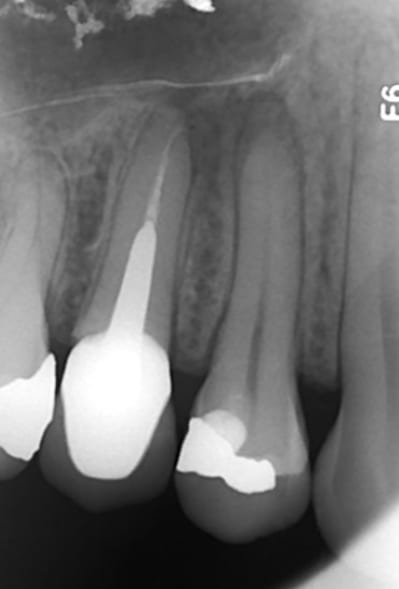

Ci joint un cas vu le 29/04/2014 pour une douleur à la mastication au niveau des prémolaires sup. droites. Douleurs à la percussion au niveau de 14 et 15. Aucune réponse au test thermique au niveau de 14.

Je décide de traiter en 1ère intention la 14 nécrosé. Les symptômes diminuent largement, mais il demeure une zone douloureuse à la palpation au niveau de la table vestibulaire (la lésion est palpable entre les deux racines 14-15).

Le patient pas très sérieux disparait avec sa provisoire durant plus d'un an...

Il refait surface en Août 2015! La lésion est toujours visible à la radio. Le kyste est toujours palpable en vestibulaire. La palpation est toujours douloureuse.

On décide de déposer la couronne et l'ic de la 15, afin de refaire le traitement canalaire des deux dents 14 et 15.

Suite au retraitment de la 15, une fistule apparait en vestibulaire. La radio cône de gutta dans la fistule montre que celui-ci remonte jusqu'à la lésion (peut être plus au niveau de l'apex de la 15?!). Comme le canal V de la 14 n'est pas obturé jusqu'à l'apex je décide de retraiter ce canal...

Patient revu ce matin, la fistule de ne referme toujours pas, et ça gonfle par intermittence selon les dire du patient, mais le cône de gutta ne remonte plus jusqu'au niveau des apex de 14 et 15... (signe de début de guérison?)

Je décide de retraiter la 15, mais cette fois-ci j'obture au MTA + cônes de gutta ; j'ai pas encore de biocéramique... :-(

Un cône beam a été prescrit, et l'étape suivante est la résection apicale si la fistule ne se referme pas la semaie prochaine!